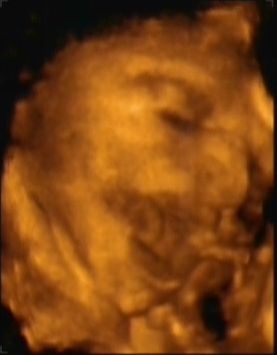

Ja és képzeljétek, ma telt le az amnio óta a 2 hét - és nem kerestek - tehát rendben vagyunk!!!!!!!!!!!!!!!!!!!!!!!!!!!!!!!!

Alig várom már a papír alapú konkrét-tuti eredményt - a kromoszómákkal együtt